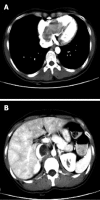

Intravenous leiomyomatosis (IVL), showing unusual growth patterns of uterine leiomyoma, is a rare neoplasm characterized by intravascular proliferation of a histologically benign-looking smooth muscle cell tumor mass, but not invading the tissue. To date, less than 300 cases have been reported and fewer than 100 cases with cardiac involvement. Imaging characteristics of IVL are still not clear so it is usually misdiagnosed before surgery. A 36-year-old woman, who had undergone hysterectomy due to hysteromyoma, presented with shortness of breath after activities. Imaging showed IVL with mass involvement of the left ovarian vein, left renal vein, left external and common iliac vein, as well as within the inferior vena cava (IVC), extending into the right atrium. The operation demonstrated that the mass had no stalk and had well-demarcated borders with the wall of the right atrium and IVC. The patient underwent a one-stage combined multidisciplinary thoraco-abdominal operation under general anesthetic. Subsequently, the pathology report confirmed IVL. IVL should be considered in a female patient presenting with an extensive mass in the right side of the heart. Imaging technology, such as echocardiogram, contrast-enhanced computed tomography and magnetic resonance imaging, can provide important information to reveal the mass, the range and path of the lesion, and relates to the surgical plan decision. Consequently, perfect and exact image examination is very necessary pre-operation.